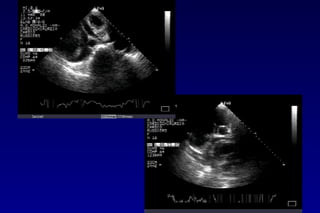

METODOLOGIA DI STUDIO

Uno studio completo del pericardio richiede diversi

approcci: parasternale asse lungo e asse corto,

apicale, sottocostale.

Uno studio completo del pericardio richiede

diversi approcci: parasternale asse lungo e

asse corto, apicale, sottocostale.

METODOLOGIA DI STUDIO VALUTAZIONE

SEMIQUANTITATIVA

• Lo spazio eco-privo solo sistolico tra i due foglietti

NON è considerato patologico

• Separazione sisto-diastolica: VP lieve, corrispondente

a 15-35cc.; se il versamento è circonferenziale: circa

300 cc.

• Se spazio eco-privo diastolico posteriore >10 mm: VP

> 500 cc.

• Se spazio eco-privo diast. post. >20mm: VP >700cc

 swinging heart (pseudo PM, movim. paradosso

siv)